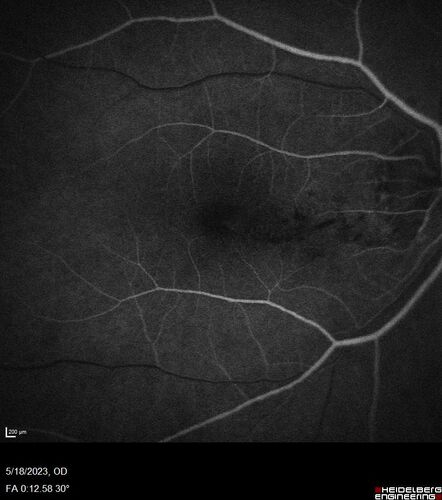

Twig (Macular) Branch Retinal Vein Occlusion with no symptoms

73 year old female with 20/25 vision and no symptoms

Twig (Macular) BRVO with edema